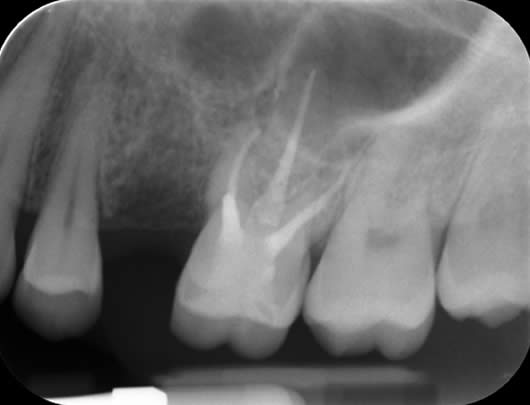

After completion of root canal retreatment

1 year review showing complete healing of the previous ‘shadow’.